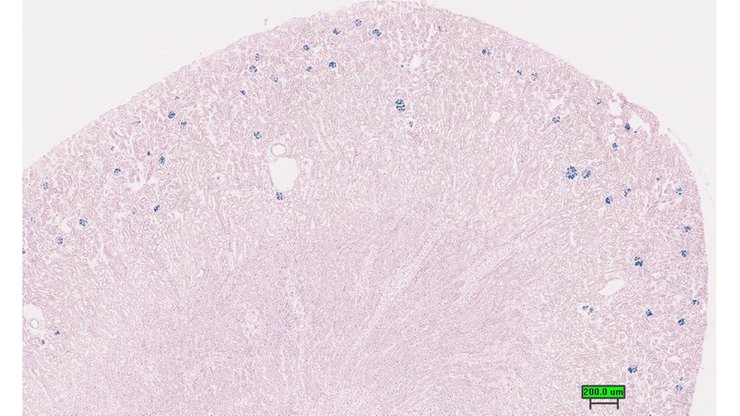

Structure Level Pattern Image Note

TS28: metanephros Present UC Davis_1871096 kidney

Specimen UC Davis_1871097: postnatal adult; Gata5tm1.1(KOMP)Vlcg/Gata5+ (more )

Note: The IMPC refers to this as a tm1b allele; when using standard nomenclature conventions, however, it is a tm1.1 allele.

TS28: metanephros Present UC Davis_1871097 kidney